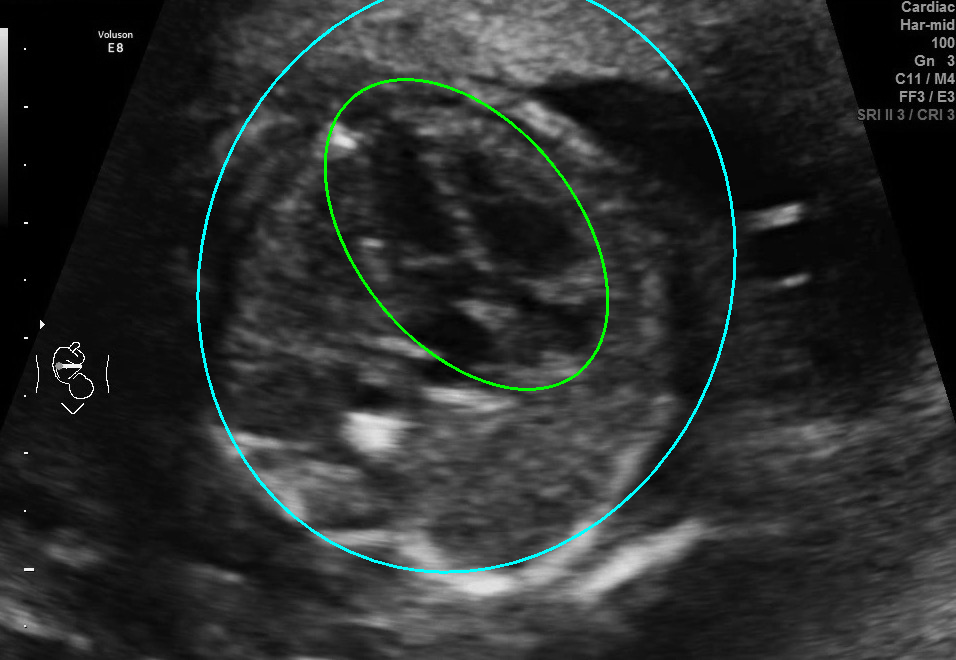

Visualization results of different methods.

Although the segmentation model trained on the fetal ultrasound dataset achieves a relative high average dice scores averaging over 0.9, the fitted ellipse highly depends on the segmentation results. As shown in the middle row of Fig. 2, the segment-based ellipse-fit method performs well when the image quality is good (first row), but the performance degrades when the segmentation is affected by image artifacts such as the acoustic shadowing (second and third row). Our proposed method is more robust to image quality and shadows. We also tried to compare to the GPN [9] with their open source code on our dataset, however, the results are not comparable to ours and those presented in Table. 1. It is difficult to conclude whether it is caused by the network itself or the training strategies. We, therefore, did not include the comparative results in this work.

As shown in Fig. 3 , both the proposed ellipse regression loss and IoU loss are necessary for ellipse detection. If the EllipseNet only supervised by IoU loss (first column), the model fails to optimize the major and minor axis separately, and the predicted ellipses degenerate into circles like the CircleNet. It is clear that the supervision of IoU loss can help to improve the prediction of location and shape (first and second row) and to correct the angle (last row).